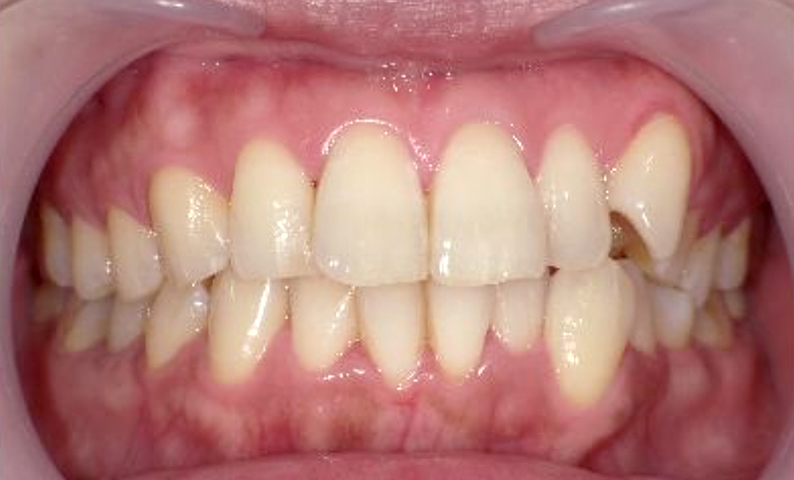

症例_002 上顎だけの部分矯正

治療期間:7ヶ月金額:30万円+税女性前歯のガタガタ上の前歯だけ

| Before | After |

|---|---|

|